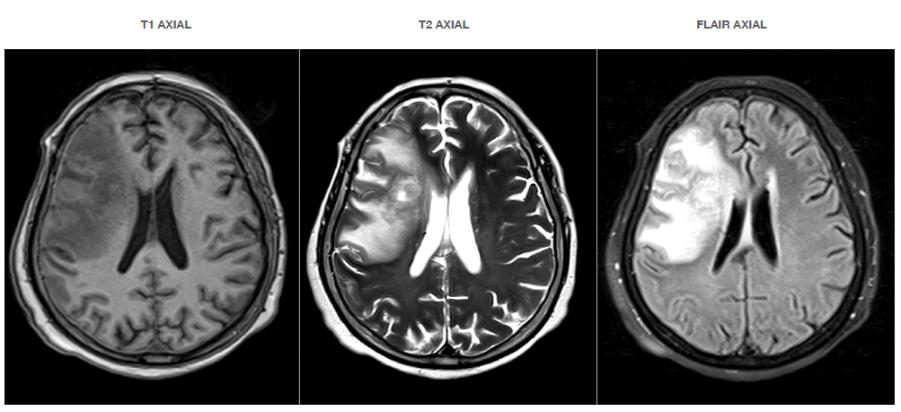

Se solicita una radiografía periapical, en la misma se observa la presencia del conducto radicular único, ancho con una sola cámara pulpar, está misma

ubicada en la corona mesiopalatina, también se puede observar la imagen radiopaca que evidencia la cúspide en garra (Fig.2).

Figura Nº2. Radiografía periapical que muestra que la pieza dentaria presenta una sola raíz y un solo conducto radicular, además presenta la imagen radiopaca de la cúspide en garra.

Fuente: Elaboración propia, septiembre 2021.